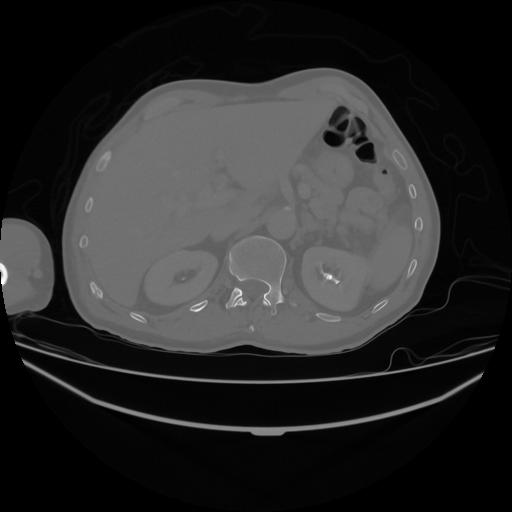

5 CUERPO,CE,Vol,1.0,CUERPO,,